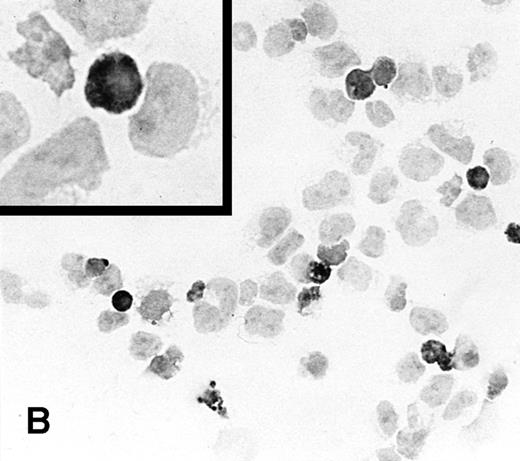

To determine the ability of an MuLV-based retroviral vector to stably infect NK cells, expression of IL-2 and Neo markers was evaluated. The efficiency of a flow-through method was determined by immunostaining for expression of the transgene. As a control, MFG-IRAP–infected NK-92 cells were used. Figure 1 shows staining for IL-2 of cultured P-NK-92 cells, which were negative for intracytoplasmic IL-2, and of transiently transduced NK-92 cells, which contained 10% to 20% stained cells. The percentage range of positive cells was determined by counting a total of 200 cells on each immunostained cytosmear prepared from three different cultures of transiently transduced NK-92 cells. These cultures were not tested by ELISA for the level of IL-2 in the supernatants because of the presence of exogenous IL-2. Instead, a culture of NK-92 cells transduced with the IRAP gene and containing 2% to 3% IRAP-positive cells by immunostaining (not shown) was tested in ELISA for the level of IRAP in the supernatant. At 72 hours posttransduction, the supernatant contained 8.4 ng IRAP/106 cells/48 h. P-NK-92 cells did not produce IRAP.

Immunostaining for IL-2 in transduced but nonselected NK-92 cells. (A) P-NK-92 cells incubated for 48 hours in the absence of exogenous IL-2 prior to staining. (B) Transduced nonselected (48 hours posttransduction) IL-2/Neo/NK-92 cells incubated for 48 hours in the absence of exogenous IL-2 prior to staining. Insert shows an IL-2–expressing NK cell (original magnification ×1,000). The staining reaction was developed with AEC, and the cells were counterstained with hematoxylin. For A and B, original magnification is ×500.

Based on this initial experience, a transduction method facilitating a high rate of gene transfer (ie, rapid binding and internalization of the virus) was sought. A recently described technique of flow-through gene transfer17 appeared to offer this advantage, and we applied it to transduction of NK-92 cells with the viral supernatants produced by CRIP cells. Transduction of 10% to 20% NK-92 cells, which was achieved in this system, allowed for subsequent selection in G418-containing medium, leading to the establishment of stably transduced NK-92 cells expressing the IL-2 gene.